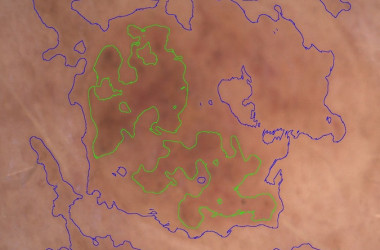

- Kamera za kožo Visioscope® PC 35

Opremljeno z vzporedno in navzkrižno polarizirano svetlobo:

- Vzporedno polarizirana svetloba vizualizira površinsko strukturo kože

- Navzkrižno polarizirana svetloba razkriva globlje plasti kože, kot so pigmentacija in vaskularne strukture

Načine osvetlitve lahko takoj spremenite s pritiskom na gumb kamere. Na podlagi zajetih slik programska oprema izvede enostavno in objektivno analizo slik gub, por in pigmentnih madežev. Popeljite svoje stranke na vizualno potovanje po obrazu in telesu.

Trakovi Sebufix® in Corneofix®, dobavljeni v praktičnih podajalnikih, se uporabljajo v kombinaciji s kamero Visioscope® za zagotavljanje jasnih vizualnih rezultatov nastajanja sebuma in luščenja kože, ki jih je strankam enostavno razložiti.

Sebufix® F 16 prikazuje nastajanje sebuma v realnem času

Corneofix® F 20 omogoča podrobno analizo deskvamacije in suhosti.